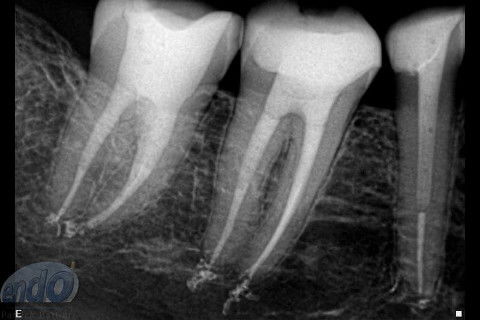

Seguem 3 casos clínicos realizados esta semana em uma cliente que está passando por um tratamento estético. O dente 47 apresentava calcificação da entradas dos canais radiculares, provavelmente, devido a uma pulpotomia realizada no passado. Desta forma, foi dedicada uma consulta de aproximadamente 2 horas para a realização deste procedimento. Os dente 45 e 46, por apresentarem canais radiculares com menor complexidade, foram tratados, simultaneamente, em sessão única com duração de aproximadamente 2 horas e 15 minutos.

Os três dentes foram tratados seguindo a técnica da FOP-UNICAMP, na qual é realizada patência e ampliação do forame apical. A instrumentação foi realizada com instrumentos rotatórios e como substância química auxiliar foram utilizados o ENDOGEL e o EDTA 17%. A irrigação ativa foi realizada com soro fisiológico. Os canais foram obturados com guta-percha e cimento PulpCanal Sealer, pela técnica de ondas contínuas de condensação.